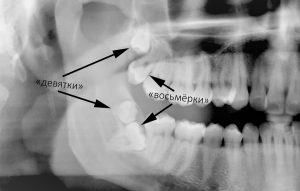

Справедливости ради, нужно заметить, что зубов мудрости может быть больше, чем четыре. Изредка встречаются не только «восьмёрки», но и «девятки» или даже «десятки». Разумеется, такой ассортимент в полости рта ни к чему хорошему не приводит.